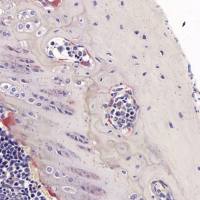

常规组织切片基本为无色透明,在一般光镜下不易观察,因此要根据组织不同结构的特异性来选择不同的实验方法。苏mu精—伊红染色法,简称HE染色法,病理技中常用的染色法之一 。苏mu精染液为碱性,使细胞核着紫蓝色;伊红为酸性,使细胞质着红色,HE染色法是组织学、病理学研究中使用广泛的技术方法,用来观察组织的基本结构。